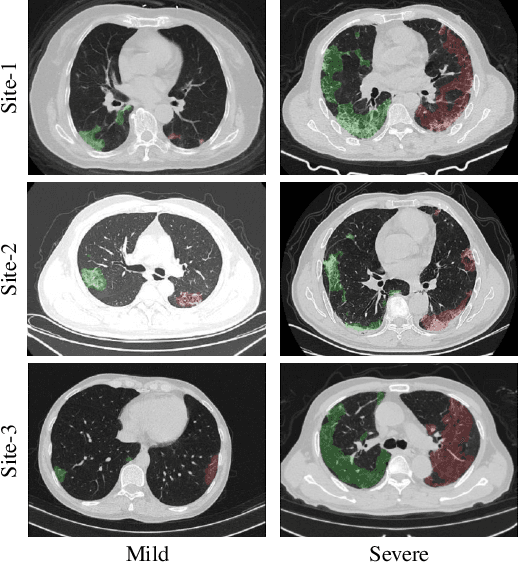

Early and accurate severity assessment of Coronavirus disease 2019 (COVID-19) based on computed tomography (CT) images offers a great help to the estimation of intensive care unit event and the clinical decision of treatment planning. To augment the labeled data and improve the generalization ability of the classification model, it is necessary to aggregate data from multiple sites. This task faces several challenges including class imbalance between mild and severe infections, domain distribution discrepancy between sites, and presence of heterogeneous features. In this paper, we propose a novel domain adaptation (DA) method with two components to address these problems. The first component is a stochastic class-balanced boosting sampling strategy that overcomes the imbalanced learning problem and improves the classification performance on poorly-predicted classes. The second component is a representation learning that guarantees three properties: 1) domain-transferability by prototype triplet loss, 2) discriminant by conditional maximum mean discrepancy loss, and 3) completeness by multi-view reconstruction loss. Particularly, we propose a domain translator and align the heterogeneous data to the estimated class prototypes (i.e., class centers) in a hyper-sphere manifold. Experiments on cross-site severity assessment of COVID-19 from CT images show that the proposed method can effectively tackle the imbalanced learning problem and outperform recent DA approaches.